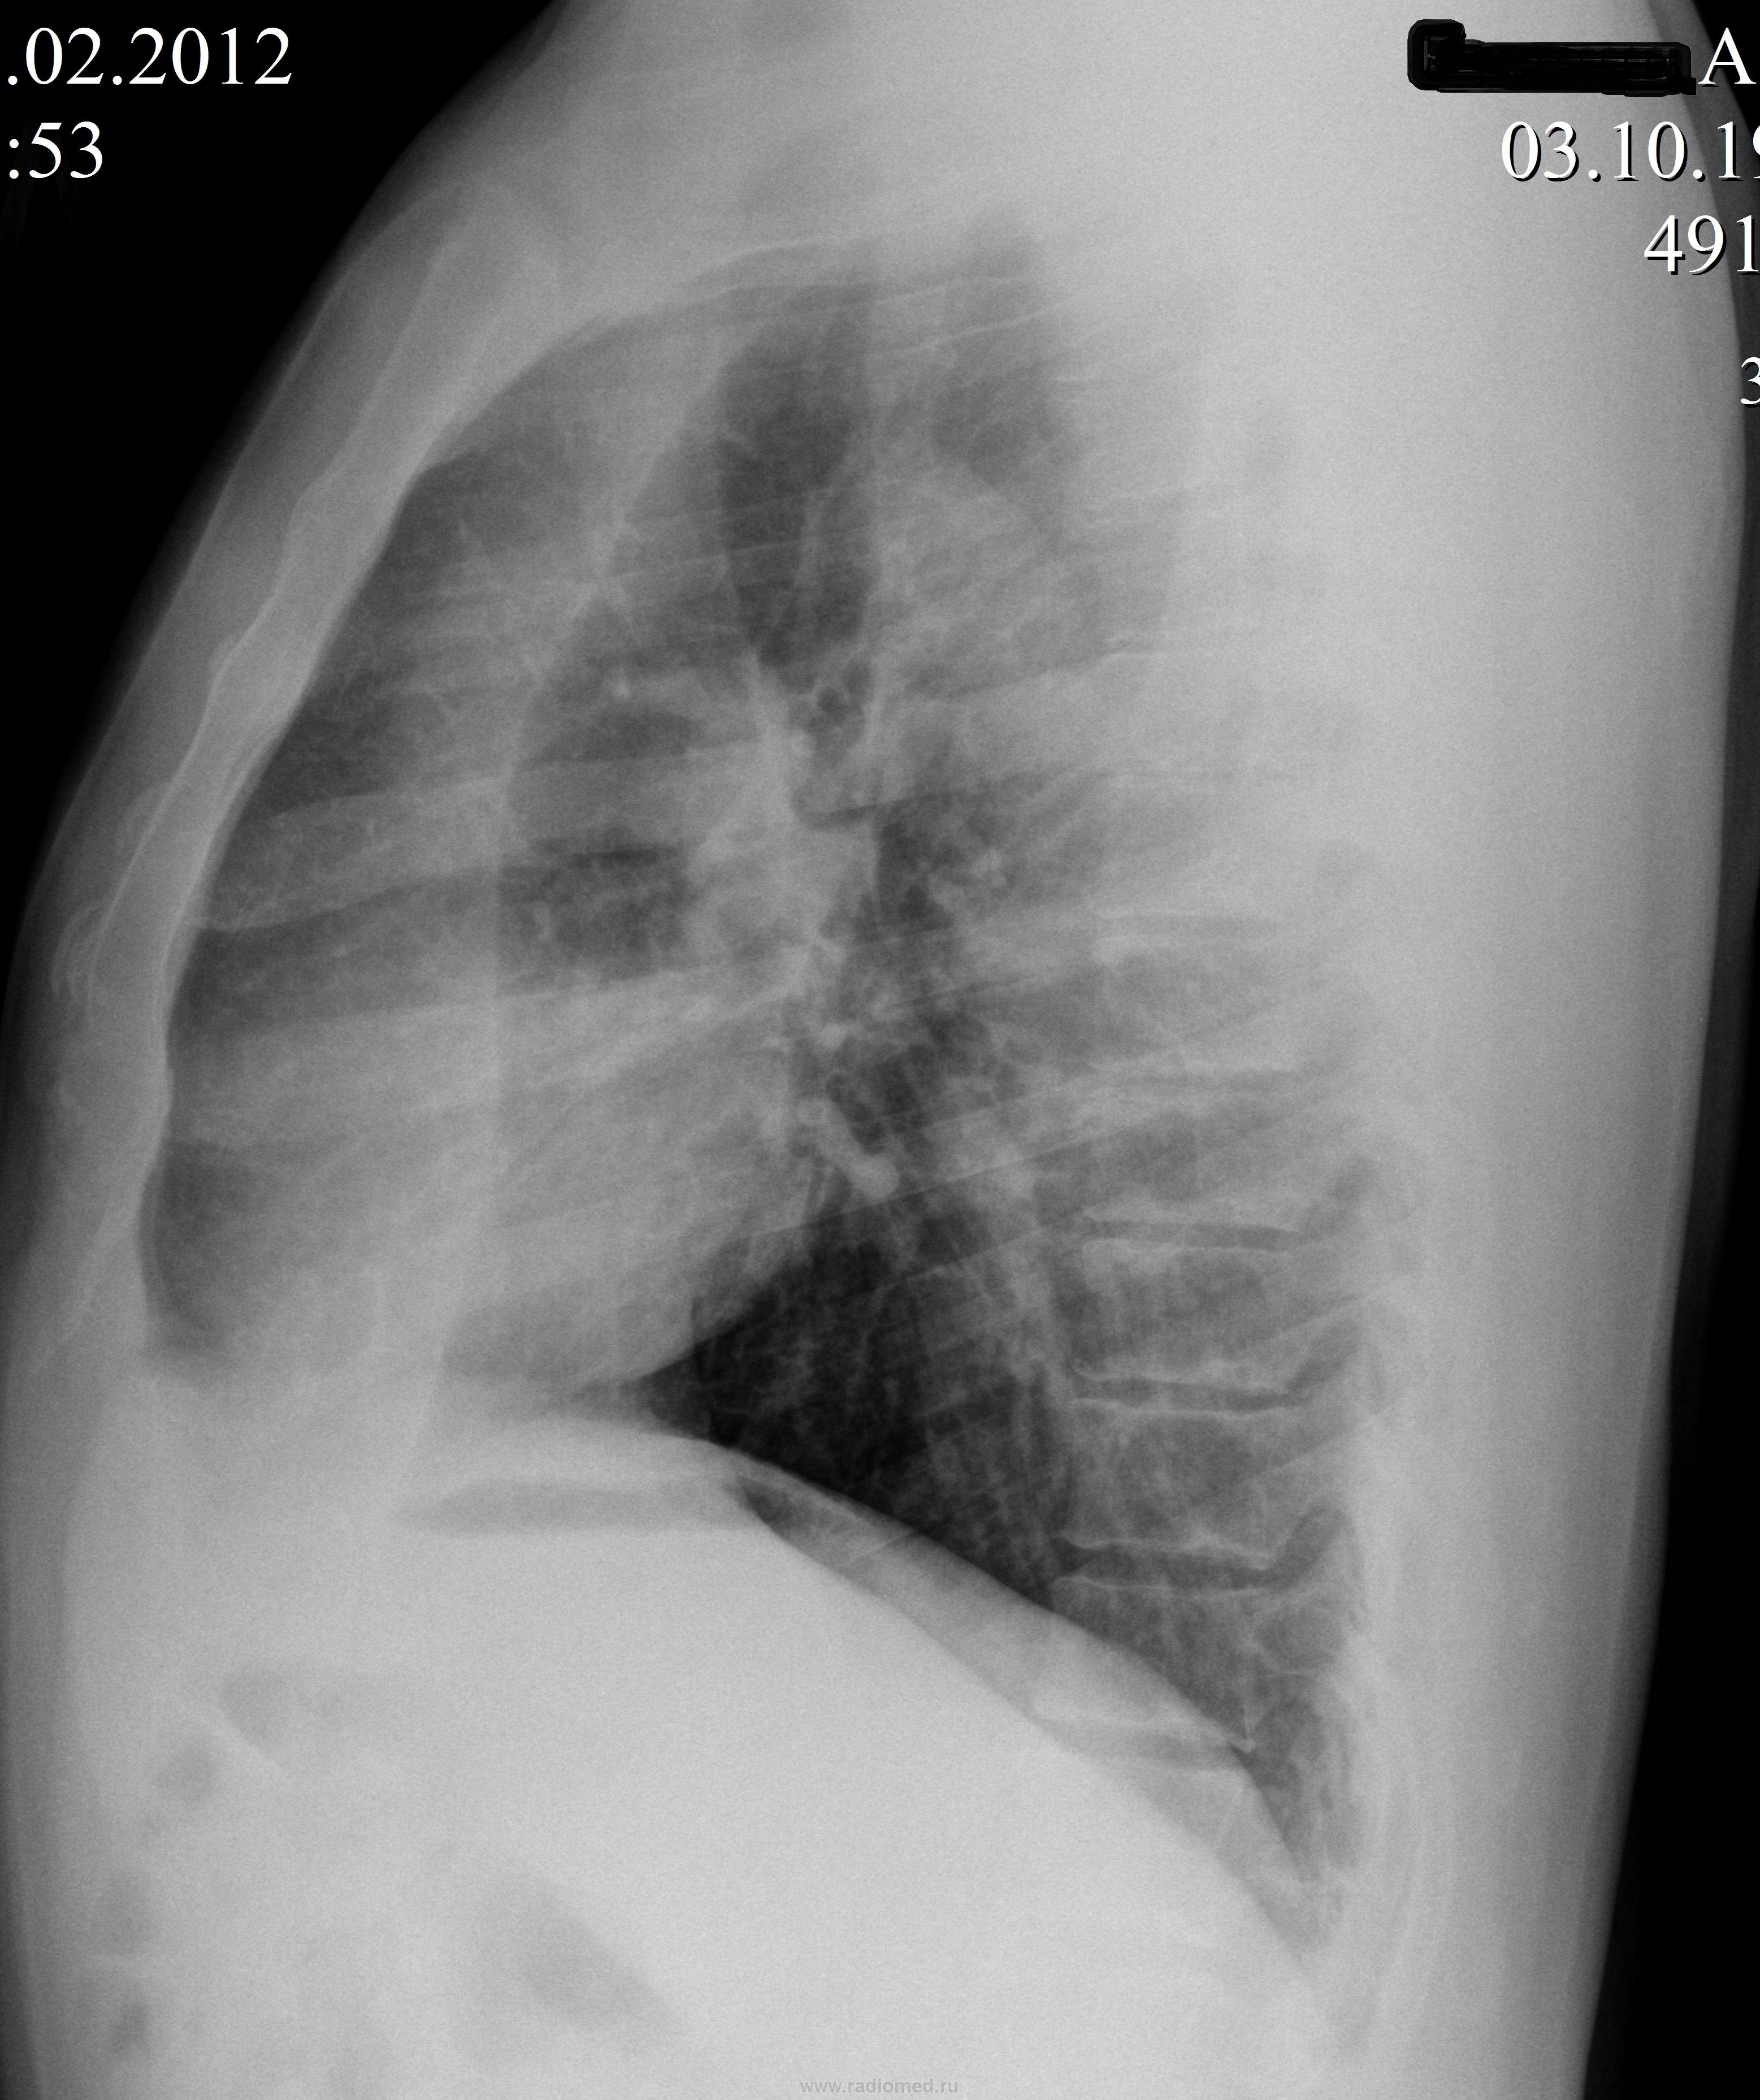

А никого не смущает почти вертикальная линия на боковом снимке? А еще средостение слегка ушло влево в сравнении с архивом.

Уважаемые коллеги, подскажите пожалуйста что за линейная тень на снимке? Кожная складка? Или это и есть тень косой м/д плевры(задняя граница ателектазированной верхней доли)?

Видимо эту тень автор наблюдения принял за тень висцеральной плевры,а то что спереди от неё - за воздух(забыв что воздух даёт просветление а не затемнение) по этому и написал в заключении "передний пневмоторакс".

а еще у него ателектаз в/доли левого легкого как на картинке в учебнике, ну и в сочетании с расширенным корнем...

Конечно случай интересный! И интересен он своей рентгенологической незавершенностью. На мой взгляд, после того, как отметено предположение об аномалии развития, на первый план выступает синдром гиповентиляции левого лёгкого, возможно, ателектаза одной из долей лёгкого. Конечно, каждый по "одёжке протягивает ножки", и в наших ограниченных условиях, без высоких технологий, конечно, мы произвели бы томограмму (ы) в районе бифуркации трахеи, и с большой степенью вероятности нашли бы "объём" в левом главном бронхе. Возможно, в другом ЛПУ целесообразно было провести бронхоскопию, да и кусочек отщипнуть от того объёма, который локализуется в левом главном бронхе.

Без томограммам, конечно, можно ошибиться, но всё же, по-моему, на исходных флюорограммах видно и Виктор Григорьевич своей схемой поддерживает, и ФБС от 06.03.2012 подтверждает – имеется поражение (видимо раковое) левого главного бронха со значительным его сужением. Потому бронхоскопист о долевом и сегментарных бронхах не пишет. Не смог до них добраться.